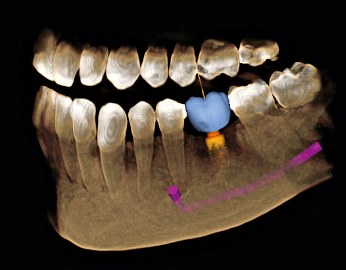

Das Digitale Volumentomogramm - DVT - ist eines der modernsten Hilfsmittel zur genauen räumlichen Darstellung und Vermessung eines Kiefers. Es wird z.B. bei der Planung von Implantaten, der Beurteilung des Zahnbettes, der Kiefergelenke oder vor chirurgischen Eingriffen angewendet. Das DVT liefert in vielen Fällen ein besseres Ergenis als die herkömmliche Röntgentechnik.

- Maßstabgetreue Darstellung (Strecken und Winkel können exakt vermessen werden)

- Beurteilung der Knochenqualität (z.B. Knochenhärte) anhand der Dichtemessung

- Die Möglichkeit, Planungs- und Bohrschablonen aufgrund der DVT-Daten anzufertigen, um während der Operation gezielt und minimal invasiv die Implantate wie vorhergeplant zu setzen.